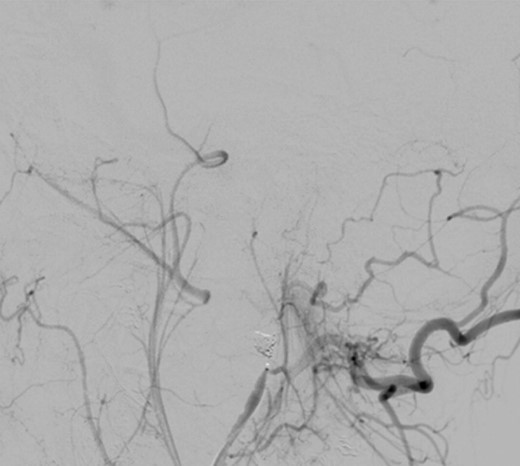

Intraoperative angiography was performed and revealed a PA in relation to the internal maxillary artery, ~1 cm posterior to the left subcondylar region (Fig. 2).

Left common carotid artery angiography in lateral views shows the PA (4.9 × 3 mm).